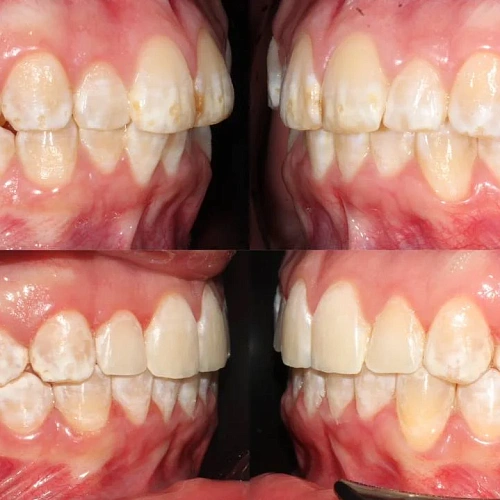

Нарушение соотношения челюстей и неправильное положение зубов — зубные ряды смыкались некорректно, зубы стояли со смещением.

Проблема: Пациентку не устраивало положение зубов и то, как смыкаются челюсти. Зубы стояли неровно, ряды сходились неправильно.

Решение: Поставили прозрачные элайнеры Click — начали с компактного набора из 20 кап. Основной комплект сделал основной объем работы, но для финальной доводки понадобился дополнительный набор из 10 кап. Итого 30 кап за 23 месяца. Результат — зубы на месте, смыкание в норме. Зафиксировали ретейнеры на обе челюсти, сняли сканы для ретенционных кап.